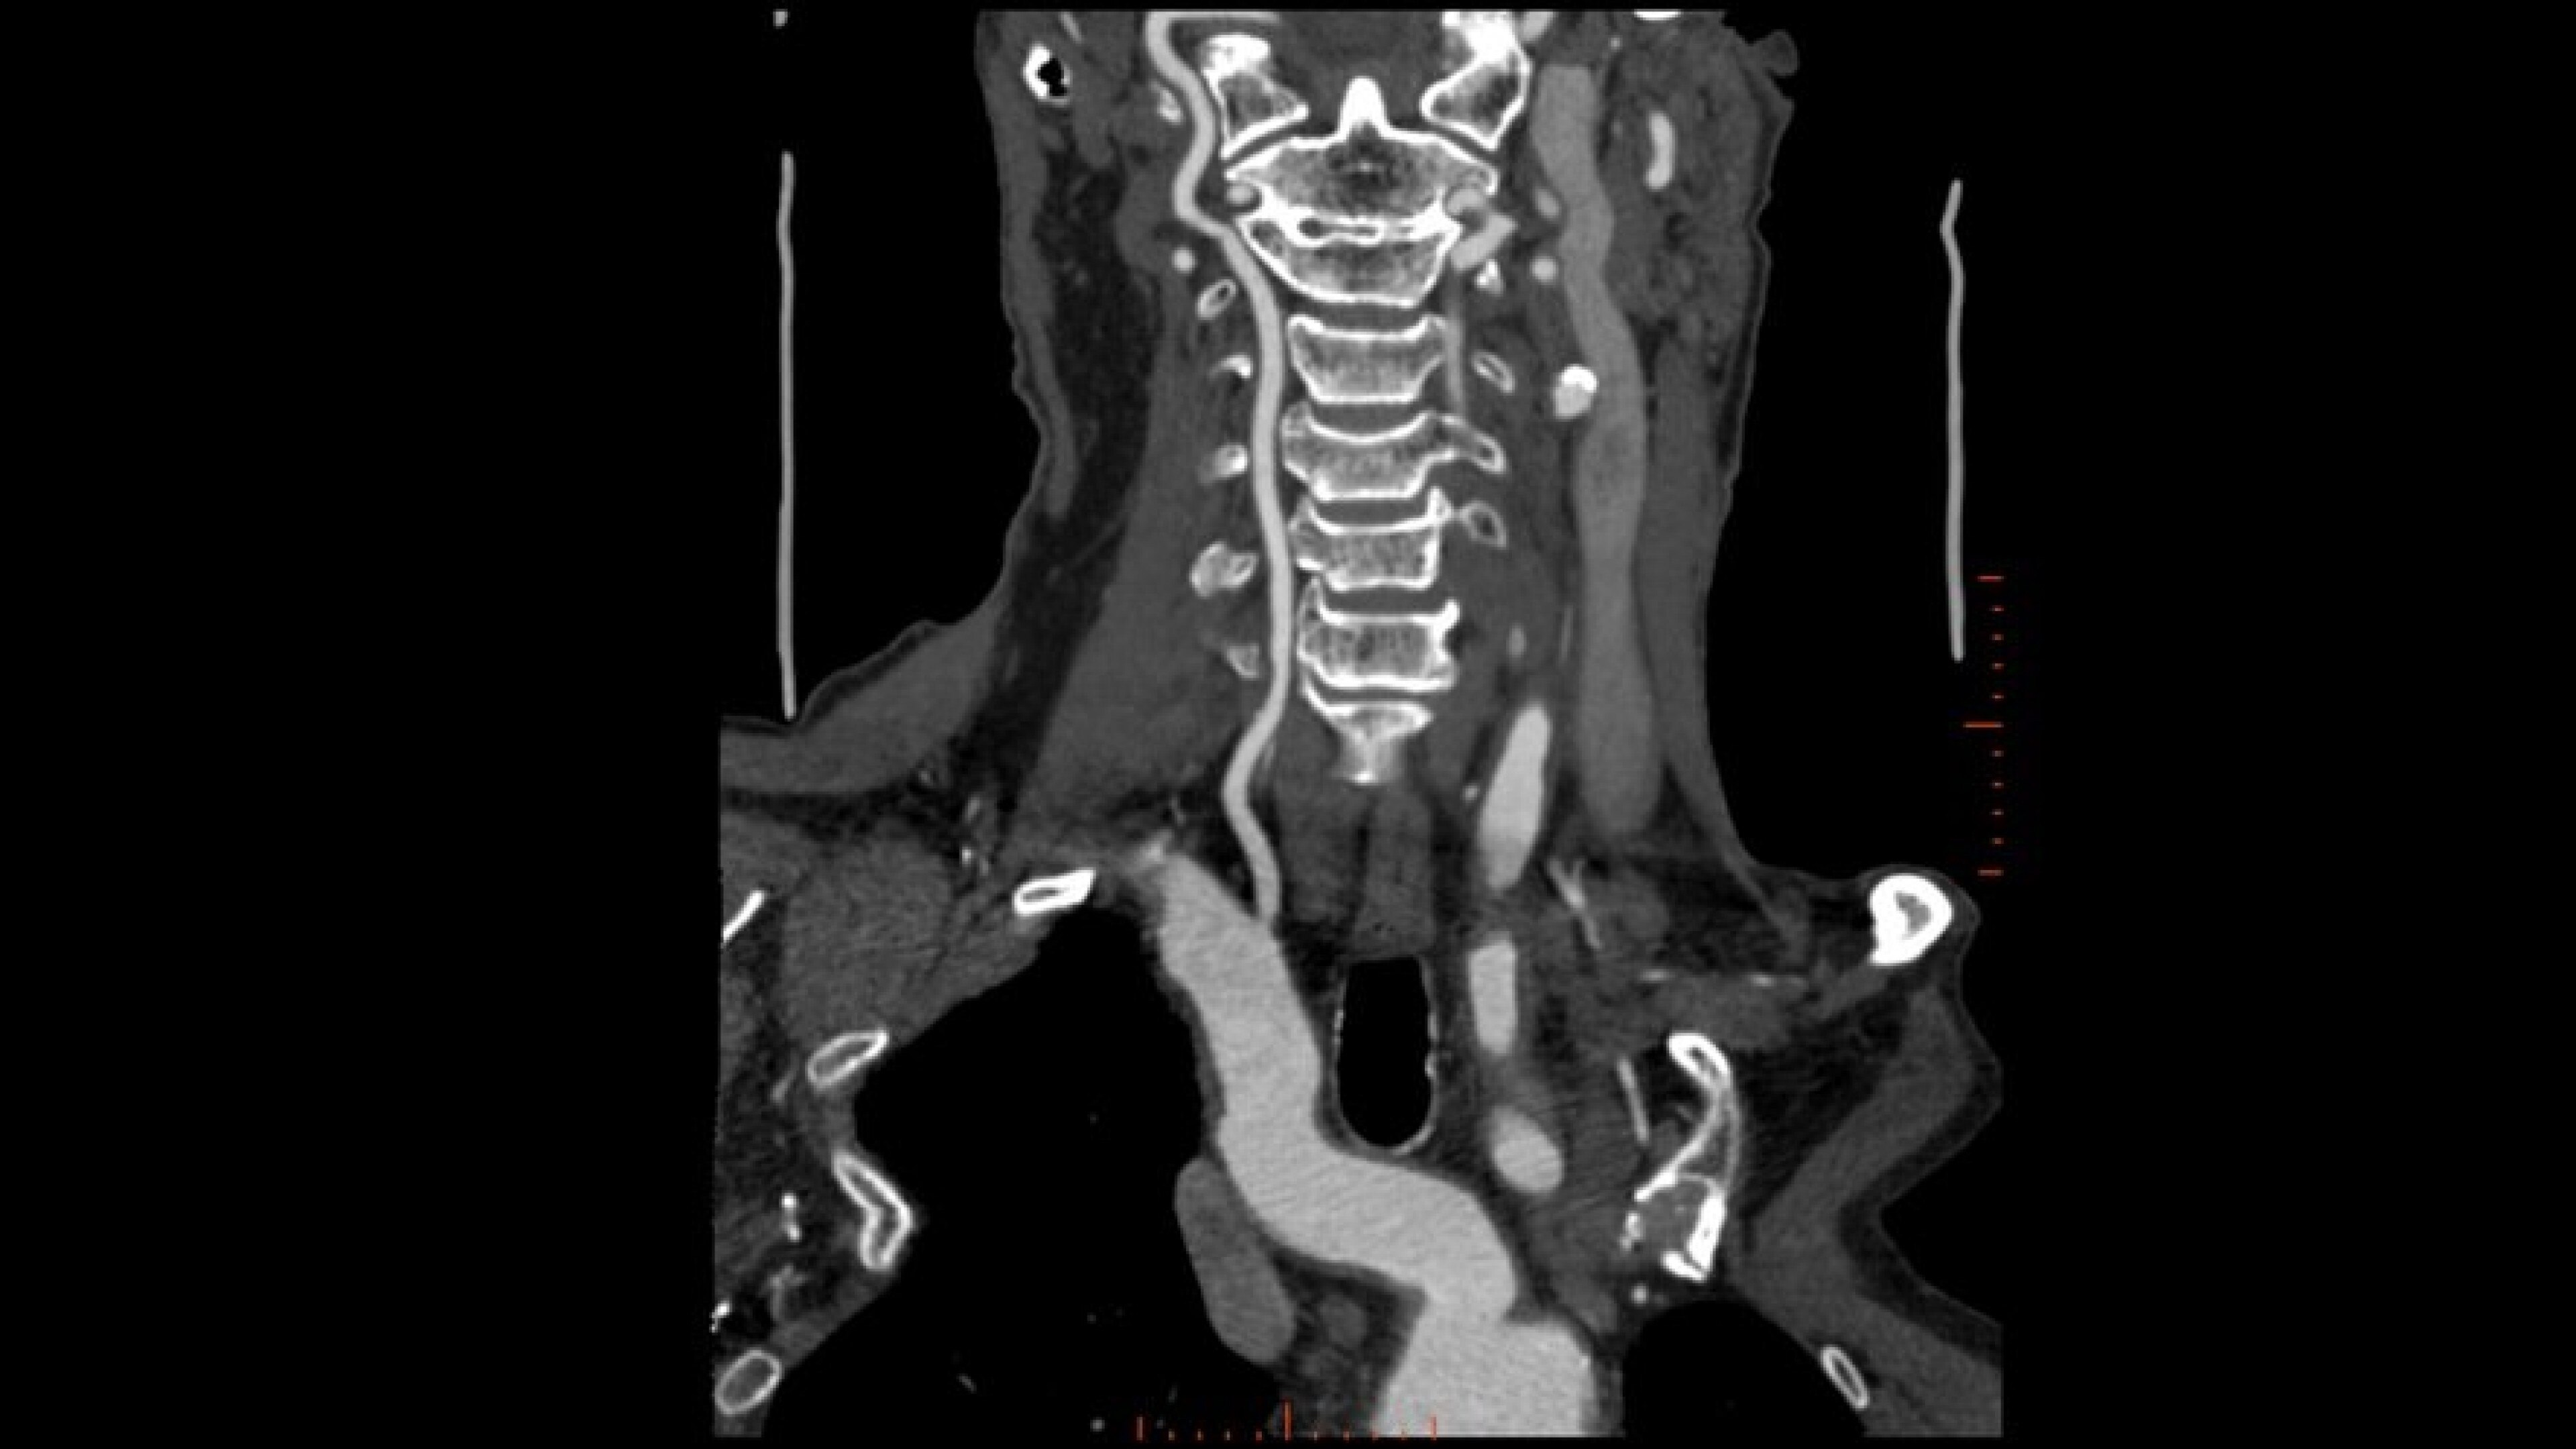

Autobone & VesselIQ Xpress

Fast and efficient vessel analysis from CT Angiography exams.

• Zero-click bone segmentation for head, neck, and other anatomy.

• Automated real-time fast tracking for all vasculature.